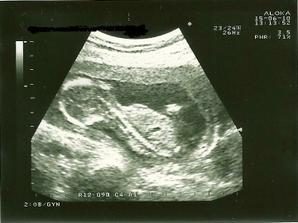

_19.7.2010 - tretia poradňa /20tt+0/, máme 322 gramov